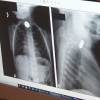

DİYARBAKIR - Soluk borusuna yabancı cisim kaçmasının özellikle 6 ay ile 3 yaş arası çocuklarda daha sık görülüyor. Diyarbakır Memorial Hastanesi Çocuk Cerrahisi Uzmanı Op. Dr. Taner Kamacı, yabancı cisim aspirasyonlarında erken tanı ve uygun ilk yardım müdahalesinin hayati öneme sahip olduğunu söyledi. Nefes borusuna herhangi bir cismin kaçması anlamına gelen "yabancı cisim aspirasyonu" çocukluk çağında daha sık görülüyor ve ölümle sonuçlanabiliyor. İstatistiklere göre, bebeklerde kazaya bağlı ölümlerin yüzde 7'si, nefes borusuna kaçan yabancı cisimlerden kaynaklan, bu nedenle yabancı cisim aspirasyonunda ilk yardım hayati önem taşıyor. "Çocuklarınızı yutabilecekleri cisimlerden uzak tutun" Ailelere çocuklarını yutabileceği cisimlerden uzak tutmalarını tavsiye eden Op. Dr. Kamacı, "Çocuklar özellikle 6 ay ile 3 yaş arası küçük bebekler eşyaları ağızlarıyla tanıdıkları için buldukları her şeyi ağızlarına götürebilirler ve bu bazen tehlikeli çok ciddi sonuçlar doğurabilir. Bazen bu ağzına koyduğu cisim nefes borusuna, ciğerine kaçabilir. Bazen yemek borusuna kaçabilir. Her ikisinde de çok ciddi tehlikeli sonuçlar ortaya çıkabilir. Bundan dolayı ailelerin küçük bebekleri olan ailelerin her zaman dikkatli olmalarını öneriyoruz. Hiçbir zaman bebekleri kuruyemişlerle, küçük parçalı oyuncaklar, küçük eşyalarla, misketlerle, madeni paralarla, iğnelerle baş başa bırakmasınlar. Mümkün olduğu kadar bu tür cisimleri çocuklardan uzak tutsunlar. ya da ulaşamayacakları yerlere koysunlar. Çocuklar, yuttuğu bir cismi ciğerine kaçırırsa yuttuğu cisim nefesin borusunu tıkarsa çok ani bir kötüleşme ve hayati risk ortaya çıkarabiliyor" dedi. "Her aile ilk yardım eğitimi alsın" Her ailenin ilk yardım eğitimi almasını önerdiklerinin altını çizen Op. Dr. Kamacı, "Diyelim evde çocuk yabancı bir cisim yuttu, bir anda nefessiz kaldı, morardı ve bu morluğu geçiyor ise tekrar nefes almaya başlamış ise o zaman ağzının içinde bir cisim varsa, bu cismi almasını ve en kısa zamanda hastaneye getirmesini istiyoruz. Ama bu nefes alamama durumu geçmediyse, çocuk mor ve nefes alamıyorsa Hastaneye getirecek bir vakit olmaz. Mutlaka kendilerinin acil bir müdahale yapması gerekmektedir. Böyle durumlarda önerdiğimiz eğer çocuk 1 yaşın altında ise çocuğumu elimizin üstüne alıp dizimizin üzerinde yüz üstü yukarıdan sırtından başına doğru süpürme hareketi ile yabancı cismin çıkmasını ya da en azından olduğu yerden yer değiştirmeyi yapabilirler. Çocuk bir yaşından büyük ise o zaman biz Hemlik manevrasını öneriyoruz. Çocuğun arkasına midenin üzerine bir elimizi yumruk yaparak diğer elimizle de yumruk yaptığımız elin üzerine baskı yapıp göğüs kısmında bulunan cismin çıkmasını sağlayabiliriz. Bu tür müdahaleleri aileler evde yapabilirler ise çocuğun hayatını kurtarabilirler. Çünkü bizim başımıza geliyor. Hasta evden hastaneye yetiştirilene kadar hayatını kaybetme ile karşı karşıya kalabilmektedir. İlk yardım ve acil müdahale çok önemli. En önemli kısım da ailelerin böyle durumda panik yapmaları. Çünkü aile, anne ya da baba panik olduğu zaman bunu yapacak cesareti de olmuyor ve o anda akıllarına bile gelmeyebilir. Sakin olsunlar ve bu gösterdiğimiz manevraları evde uygulasınlar. Ama eğer çocuk nefesini alıyorsa ve öksürünce biraz zorlanıyor ise evde yapabilecekleri bir şey yok. En yakın sağlık birimine getirmesini öneriyoruz" diye konuştu.